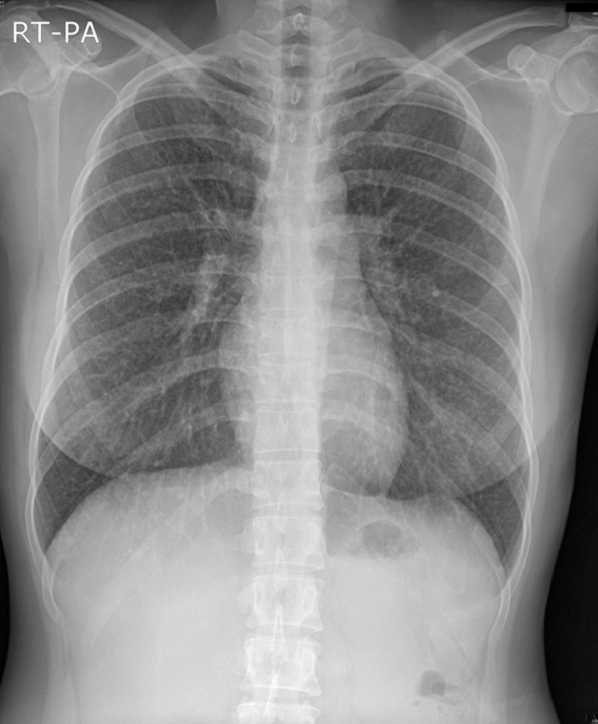

34¼¼ ¿©È¯

Ưº°ÇÑ Áõ»ó ¾øÀÌ CXR »ó ÀÌ»ó¼Ò°ßÀÌ ÀÖ´Ù°í Refer µÈ Case ÀÔ´Ï´Ù.

AFB Negative ÀÔ´Ï´Ù.

Chest PA, Chest CT »çÁøÀÔ´Ï´Ù.